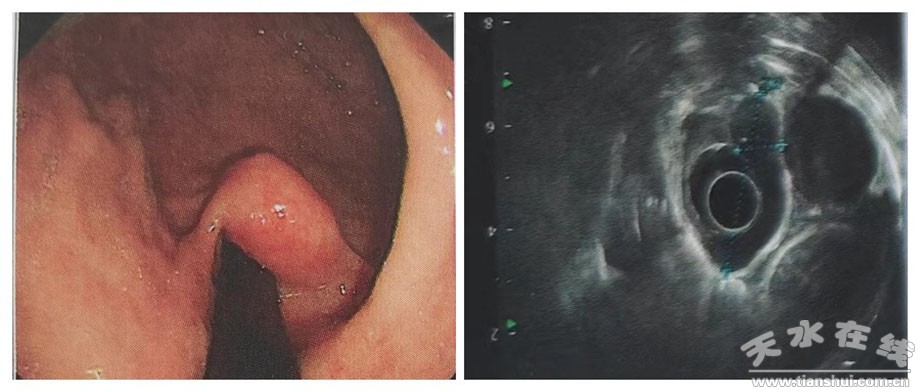

今年52歲的劉女士,因腹部不適就診首都醫(yī)科大學(xué)北京同仁醫(yī)院,行胃鏡檢查,發(fā)現(xiàn)賁門翻轉(zhuǎn)位可見似黏膜下腫樣隆起,約2.0*1.5cm;超聲內(nèi)鏡提示病變位于胃壁第四層,偏低回聲,測量大小約3.5*1.0cm。

7月4日13:30在市一院內(nèi)鏡中心和麻醉科的協(xié)助下,進(jìn)行全身麻醉+氣管插管,手術(shù)過程中,在蘭大一院姬瑞主任醫(yī)師的指導(dǎo)下,消化內(nèi)科茍金平主任醫(yī)師、贠嘉威主治醫(yī)師、張云主治醫(yī)師及內(nèi)鏡室護(hù)士的協(xié)調(diào)配合下,在內(nèi)鏡下使用Dual-knife切開腫瘤表面黏膜層,暴露白色瘤體,后沿黏膜下層剝離瘤體,并予以圈套器、活檢鉗輔助牽引完整挖除瘤體,剝離過程中出現(xiàn)穿孔,予以9枚鈦夾封閉創(chuàng)面。患者右側(cè)胸壁、顏面部可觸及捻發(fā)感,遂啟動多學(xué)科協(xié)作(MDT),請胸外科、超聲科、放射科、重癥醫(yī)學(xué)科等多學(xué)科專家術(shù)中會診,考慮皮下氣腫。術(shù)中嚴(yán)密觀察患者,生命體征平穩(wěn),手術(shù)成功,實現(xiàn)了以最小創(chuàng)傷達(dá)到最佳治療效果的目的。為保證患者安全,術(shù)后轉(zhuǎn)重癥醫(yī)學(xué)科觀察。術(shù)后2小時,患者順利拔出氣管插管,神志清楚,病情平穩(wěn),未訴腹痛、腹脹,無嘔血、黑便。術(shù)后15小時轉(zhuǎn)回消化內(nèi)科普通病房進(jìn)行術(shù)后恢復(fù)治療,目前患者情況良好,近日準(zhǔn)備出院。